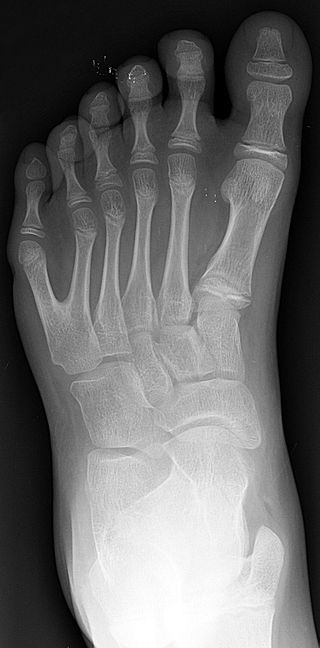

Полидактилия или многопалость – врожденная патология конечности, которая проявляется наличием дополнительных пальцев. Чаще всего дополнительными пальцами выступают мизинцы или большие пальцы.  Аномалия может сочетаться с прочими патологиями опорно-двигательного аппарата.

Заболевание проявляется сразу после рождения ребенка и чаще всего характеризуется удвоением мизинца на кистях рук или является вторым мизинцем. Дополнительные пальцы могут иметь абсолютно нормальную структуру. У некоторых пальцы не имеют костной основы и представляют собой нефункционирующие мягкотканые формирования на кожной ножке или выглядеть как удвоение ногтевой фаланги.  При такой патологии нарушается моторная функциональность руки.

Определить заболевание можно с первых мину после рождения ребенка. Диагностику заболевания проводит детский травматолог. Врач должен определить степень функциональных и анатомических аномалий и установить вариант патологии. Для определения степени повреждения костно-суставной системы проводят рентгенографию пораженной конечности. Дополнительно необходима консультация генетика.